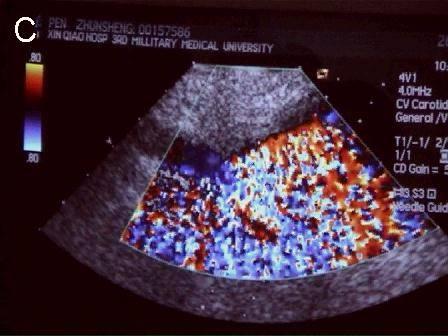

A 连接三联管及穿刺针准备 B 超声引导下注射针进入瘤腔底部(箭头处) C 经注射针注入盐水出现超声频闪现象; D 远端瘤腔内血栓逐渐形成; E 远端、近端瘤腔内血栓完全形成; F 术后足背动脉血流良好. 国内首家开展,例数最多,疗效肯定。此技术在全国推广应用。处于全国领先水平。 |